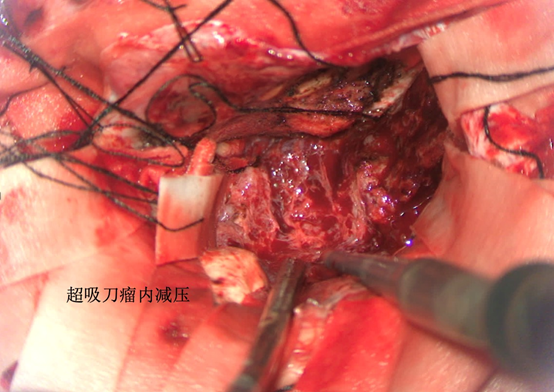

前颅窝底脑膜瘤常起源于前颅底筛骨筛板处的硬膜,瘤体多为双侧生长,少数为偏侧生长,女性稍多于男性。肿瘤可累及鸡冠和蝶骨平台的任何区域,是前颅窝肿瘤中最多见的一种。因为肿瘤位于前颅窝底,额叶在功能上属于“哑区”,患者就诊发现肿瘤时瘤体多已巨大。主要症状可有颅内压增高症状、视力减退、癫痫以及精神症状等。该患者主因“左眼失明10个月,头痛3个月”就诊。术中采用双额冠状开颅,左侧为主,由于肿瘤体积巨大,术中切除少许薄层额叶脑组织,边离断基底、边瘤内减压,分块切除肿瘤,最终探查肿瘤基底主要位于鸡冠、筛板、蝶骨平台、鞍结节、前床突处硬膜,术中见肿瘤供血主要来源于前颅窝底硬膜及大脑前动脉分支,术中仔细辨认供血动脉、过路血管,大脑前动脉及其分支保护完好,术中见视神经、视交叉受压明显,尤其是左侧视神经已缺血苍白,最终达Simpson II级切除。术者体会,该患者术前行多模态重建,可见瘤表数条粗大的静脉,术中切莫过早离断肿瘤的引流静脉,以防因引流不畅致瘤体肿胀出血;术前行多模态重建,利于鉴别供血动脉、过路血管,早期离断供血动脉更利于肿瘤切除;该类肿瘤基底一般较为广泛,不能盲目离断基底,尤其是近鞍结节处,可以于中线处离断基底,进入第一间隙后向两侧探查并保护视神经,待充分缩小瘤体看清楚毗邻的血管神经后再将其完全切除;术毕做好多层颅底重建以防脑脊液漏。另外,该患者术前左眼失明已达10个月,术后第1天即有光感,术后1月复查左眼视力可达50cm内数指,这在临床中非常少见,对于此类病人,不要轻易放弃挽救视力的任何机会。